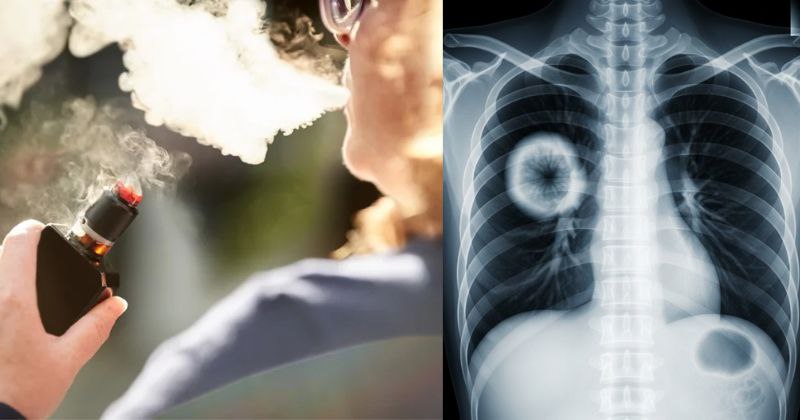

Vapeurs sucrées, dégâts amers : quand les arômes des e-cigarettes détruisent les poumons